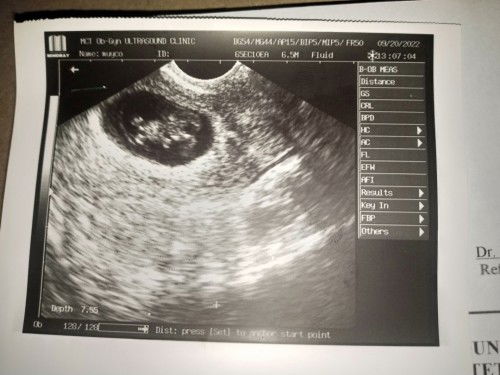

Mababa po si baby or hindi?

Na papraning po kasi ako since pinag bed rest ako at duphaston. 1st time pregnancy ko po.

hindi naman siguro mi. baka meron lang nakita na contractions during your ultrasound. ganun din kasi sakin nung mga 8 weeks ako, although wala naman po ako bedrest. sundin nyo lang payo ng doc mi para safe kayo ni baby 😊